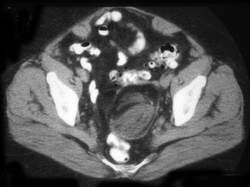

45岁女性患者,自觉腹部胀痛就诊,无发热,血象正常。B超提示左侧附件占位,行CT检查,如图所示,盆腔内见低密度肿块影,其内密度不均,最低CT值约为-150...

问题 45岁女性患者,自觉腹部胀痛就诊,无发热,血象正常。B超提示左侧附件占位,行CT检查,如图所示,盆腔内见低密度肿块影,其内密度不均,最低CT值约为-150.0hu。你认为最佳答案是 ( )

选项 A、卵巢异位妊娠 B、卵巢粘液癌 C、卵巢皮样囊肿 D、卵巢结核 E、卵巢粘液瘤

答案 C